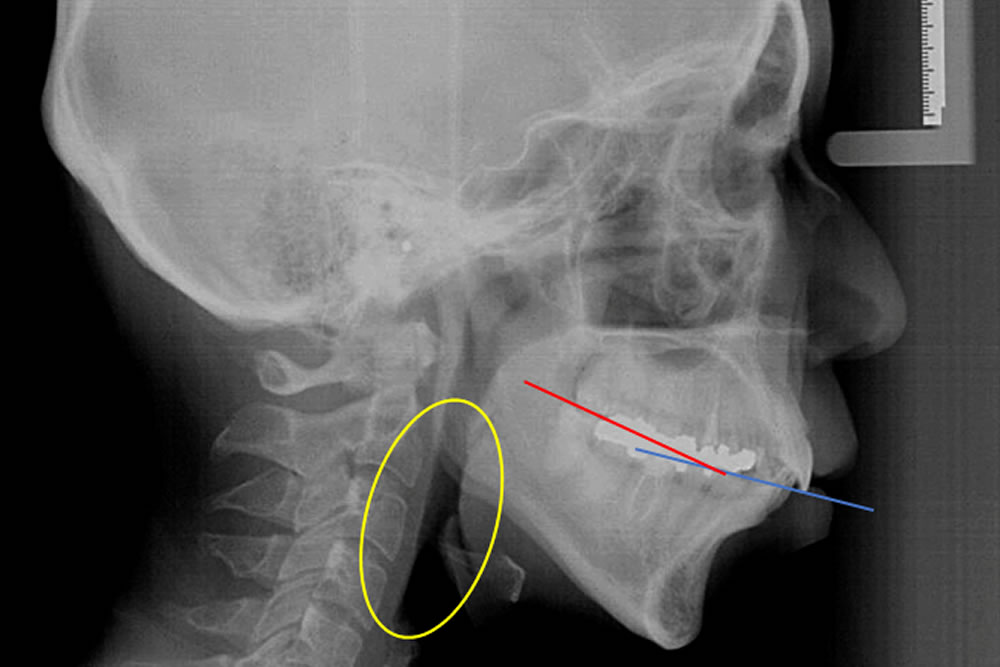

セファロレントゲンによる分析

▼画像はクリックで拡大します

- N –S –Ba(脳頭蓋角)が小さくなった(N –S –Ba:136.9→132.5)

- PNS(後鼻棘点)が挙がった(FH –PP:0.5→3.7)

- pm-ad2が改善(18.7→19.3) →上咽頭部が拡がった

【N-S-Baとは】

脳頭蓋角のことで、図中の青線の角度です。一般的に下顎後退の骨格では大きく受け口の骨格では小さくなります。骨格的な改善がみられると脳頭蓋角が変化すると考えられます。

【PNSとは】

後鼻棘点(黄色の点)のことで、上顎骨が後方回転すると下方に下がります。

【Pm-ad2とは】

図中の赤線の間の距離で、広い方が鼻呼吸環境が良くなります。